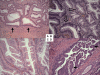

Methods: By immunohistochemistry, we assessed COX-2 expression in 24 hyperplastic polyps, 7 sessile serrated polyp/adenomas (SSA), 5 mixed polyps with SSA and adenoma, 27 traditional serrated adenomas, 515 non-serrated adenomas (tubular adenoma, tubulovillous adenoma and villous adenoma), 33 adenomas with intramucosal carcinomas, 96 adenocarcinomas with serration (corkscrew gland) and 111 adenocarcinomas without serration.

Results: Strong (2+) COX-2 overexpression was more common in non-serrated adenomas (28% = 143/515) than in hyperplastic polyps (4.2% = 1/24, p = 0.008) and serrated polyps (7 SSAs and 5 mixed polyps) (0% = 0/12, p = 0.04). Furthermore, any (1+/2+) COX-2 overexpression was more frequent in non-serrated adenomas (60% = 307/515) than in hyperplastic polyps (13% = 3/24, p < 0.0001) and serrated polyps (SSAs and mixed polyps) (25% = 3/12, p = 0.03). Traditional serrated adenomas and non-serrated adenomas showed similar frequencies of COX-2 overexpression. Regardless of serration, COX-2 overexpression was frequent (approximately 85%) in colorectal adenocarcinomas. Tumor location was not significantly correlated with COX-2 overexpression, although there was a trend towards higher frequencies of COX-2 overexpression in distal tumors (than proximal tumors) among hyperplastic polyps, SSAs, mixed polyps, traditional serrated adenomas and adenocarcinomas.

Conclusion: COX-2 overexpression is infrequent in hyperplastic polyp, SSA and mixed polyp with SSA and adenoma, compared to non-serrated and serrated adenoma. COX-2 overexpression becomes more frequent as tumors progress to higher grade neoplasias. Our observations suggest that COX-2 may play a less significant role in the serrated pathway of tumorigenesis; however, COX-2 may still play a role in later stage of the serrated pathway.